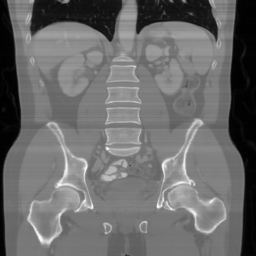

| Ground Truth | Input | DDS-100 [chungdecomposed] | DDS-200 [chungdecomposed] | NERD-P (Ours) |

| PSNR = dB | PSNR = 14.56 dB | PSNR = 37.42 dB | PSNR = 37.81 dB | PSNR = 39.15 dB |

![]() |

| PSNR = dB | PSNR = 15.58 dB | PSNR = 34.28 dB | PSNR = 34.67 dB | PSNR = 35.83 dB |

| PSNR = dB | PSNR = 12.43 dB | PSNR = 36.20 dB | PSNR = 36.56 dB | PSNR = 37.23 dB |

Main results: In Table 1, we present quantitative results and in Figure 2, we show visualizations in the axial, coronal, and sagittal planes. Our methods consistently outperform the second-best baseline across most views, achieving nearly 1 dB higher PSNR on average. Despite incorporating a few additional input updates to enforce data consistency, our method reaches competitive performance with only 30 sampling steps. Based on the visualizations, we observe that DDS introduces slight artifacts along the horizontal direction, particularly noticeable in the coronal and sagittal views. In contrast, our method produces cleaner reconstructions with fewer artifacts in these orientations.